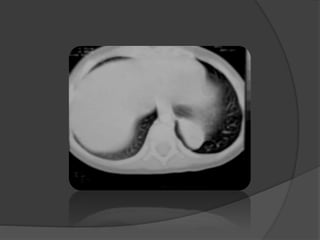

 Le scanner thoracique: confirme le diagnostic

Le lobe atteint = hyperclair et hypovascularisé

 Plus sensible:

 Aspect caractéristique des structures vasculaires

étirées et grêles

 Localisation

 Étiologie

 Diagnostic différentiel

• 72.

Imagerie  Le scannerthoracique: confirme le diagnostic Le lobe atteint = hyperclair et hypovascularisé  Plus sensible:  Aspect caractéristique des structures vasculaires étirées et grêles  Localisation  Étiologie  Diagnostic différentiel